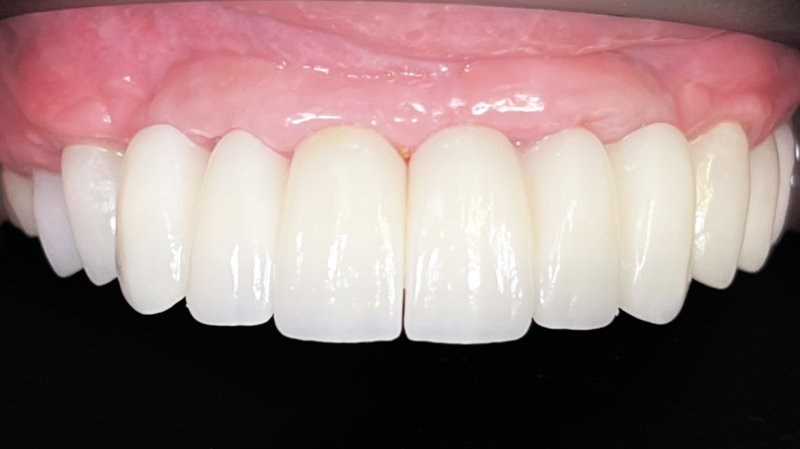

I want to share a case I’m particularly proud of. My homie AJ Marbeh in San Diego took this case from start to finish. After taking the online GBR course by David Wong he crushed it with this difficult case and he used Implant Club fixtures. Brings a tear of happiness to my eye. LOL but seriously, Love this case!